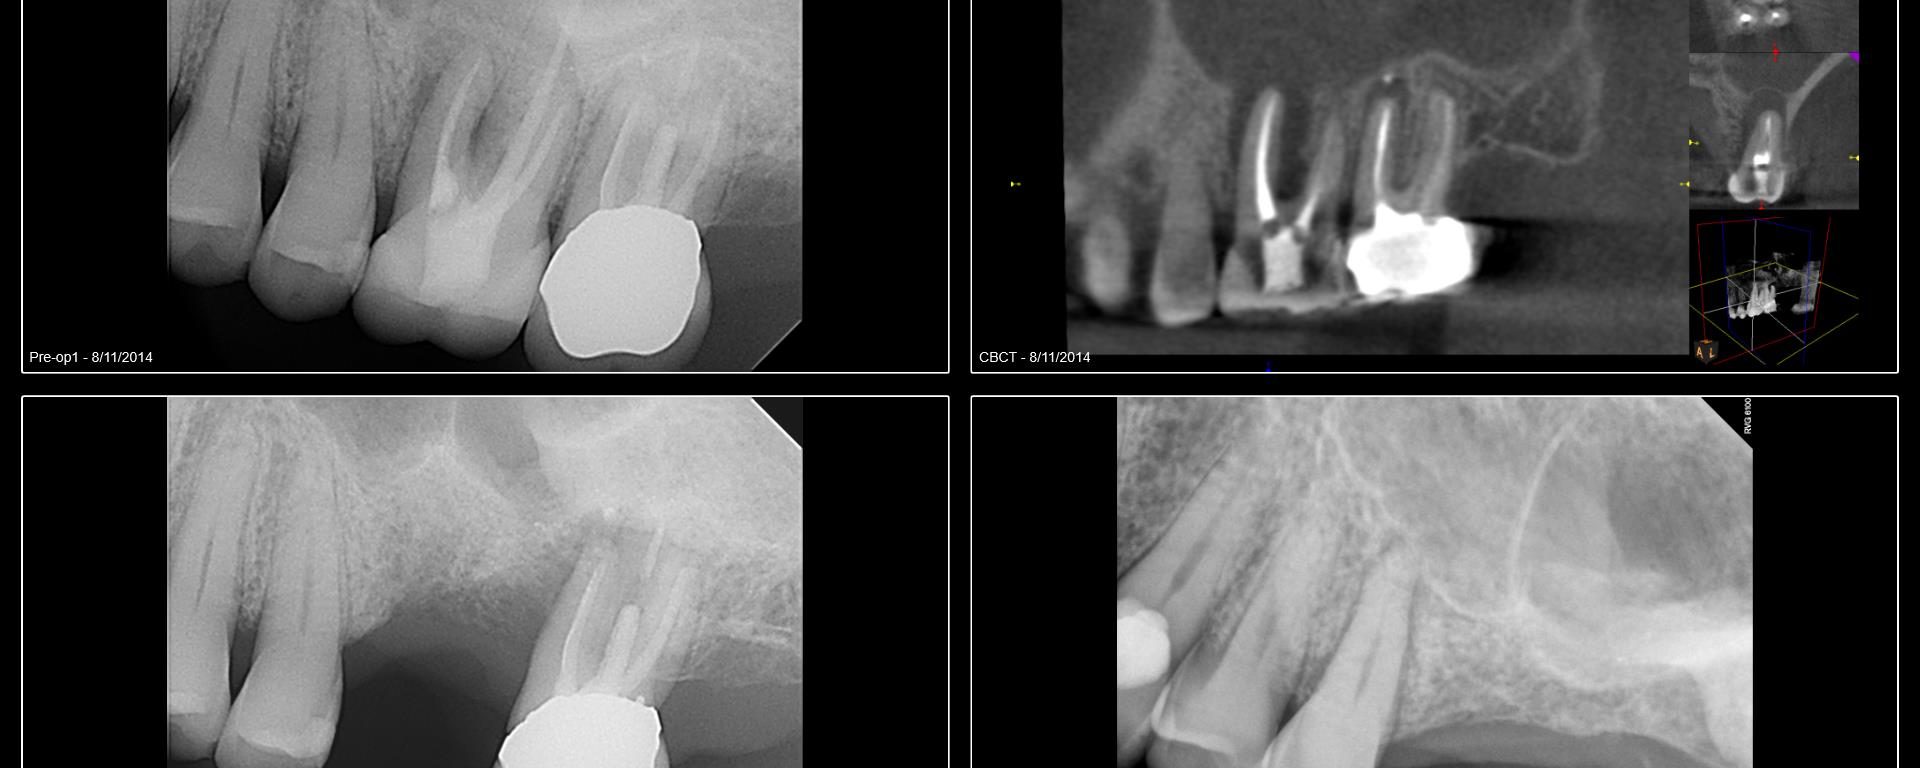

I began seeing this patient in 2014. Tooth #14 was diagnosed with a vertical root fracture at that time and the tooth was removed and the site grafted. He then presented in 2015 with a VRF of #15. It was removed and we discussed an implant in the #14 site. He did not follow up […]